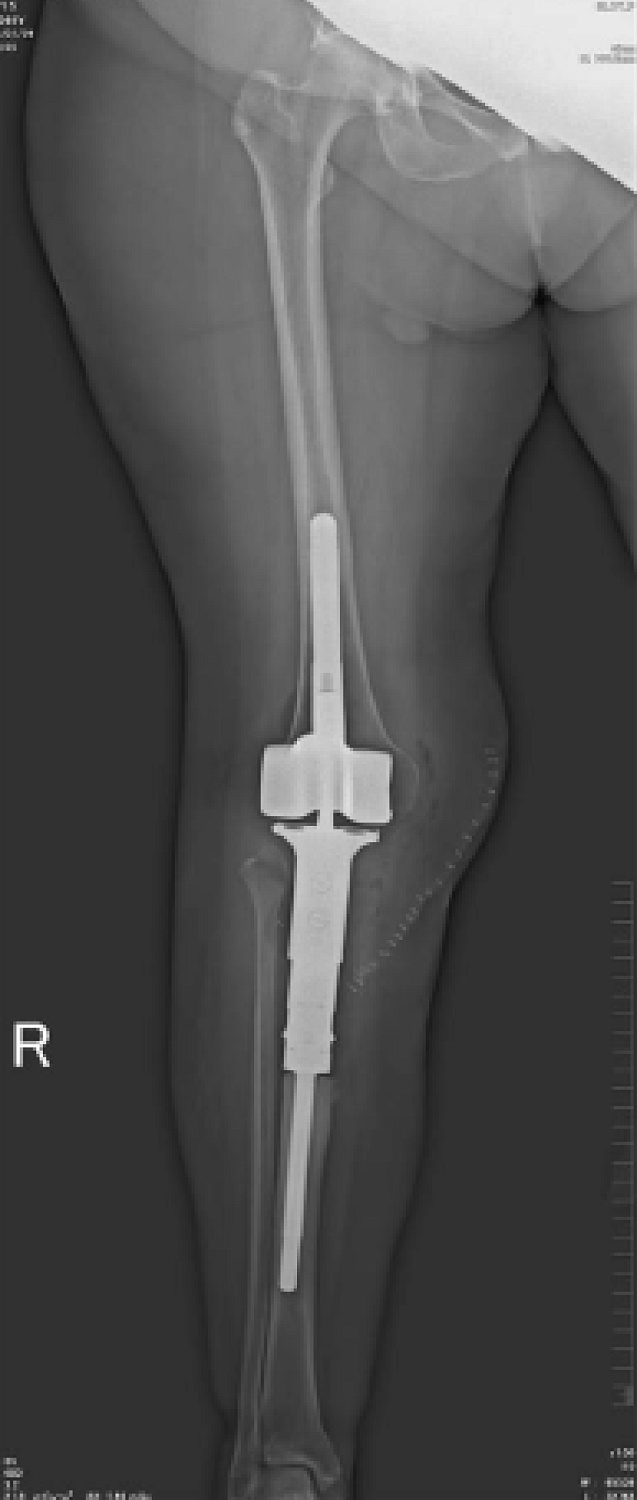

- Различные режимы съемки: рентгенография, рентгеноскопия, линейная томография, томосинтез, сшивка